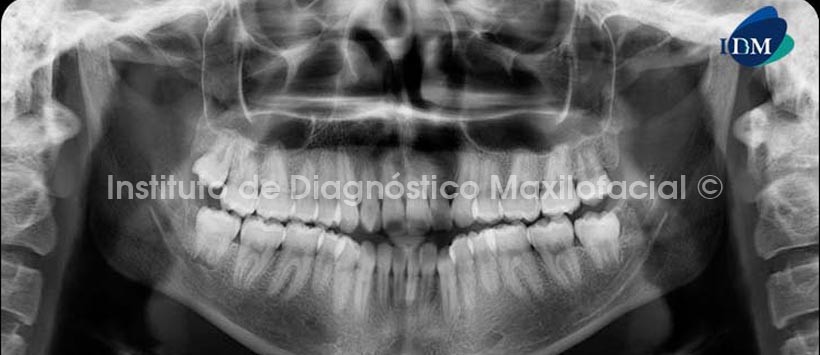

A la radiografía panorámica observamos la alteración en la morfología coronaria de la pieza 1.2 y la reabsorción radicular externa de las piezas 1.5, 2.1, 2.2 y 2.5 además de la presencia generalizada de cálculos pulpares en el maxilar superior. (Fig. 1)